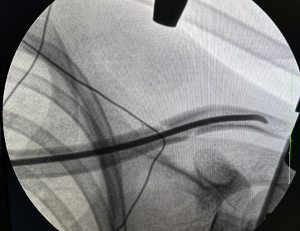

小周父母实在是发愁,到处打听,了解到了我院骨科可以进行微创手术治疗,切口小,恢复快,于是将孩子带到我院就医。我院骨科丁晔医师查看后,对患者采取微创闭合复位经皮弹性髓内钉内固定术。手术属于微创手术,仅需0.5cm的小切口从锁骨远端或锁骨近端为进针点,利用特殊器械及正骨手法,然后用弹性髓内针在锁骨髓腔内穿针固定,可以让骨折的锁骨恢复到正常形态和功能。小周的手术非常成功,患者家属很满意,悬着的心也终于放下了。

一0.5cm大小的微创切口

微创髓内针固定